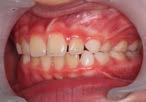

Case treated with EF Classe II Slim

Treatment time: 12 months

Enzo

• Class II 1 • Predisposition to DMD• Skeletal Class II with maxillary proalveolia and mandibular retrognathia

• Lingual dysfunction during swallowing

Before wearing EF Class II Slim

After 12 months wearing EF Class II Slim